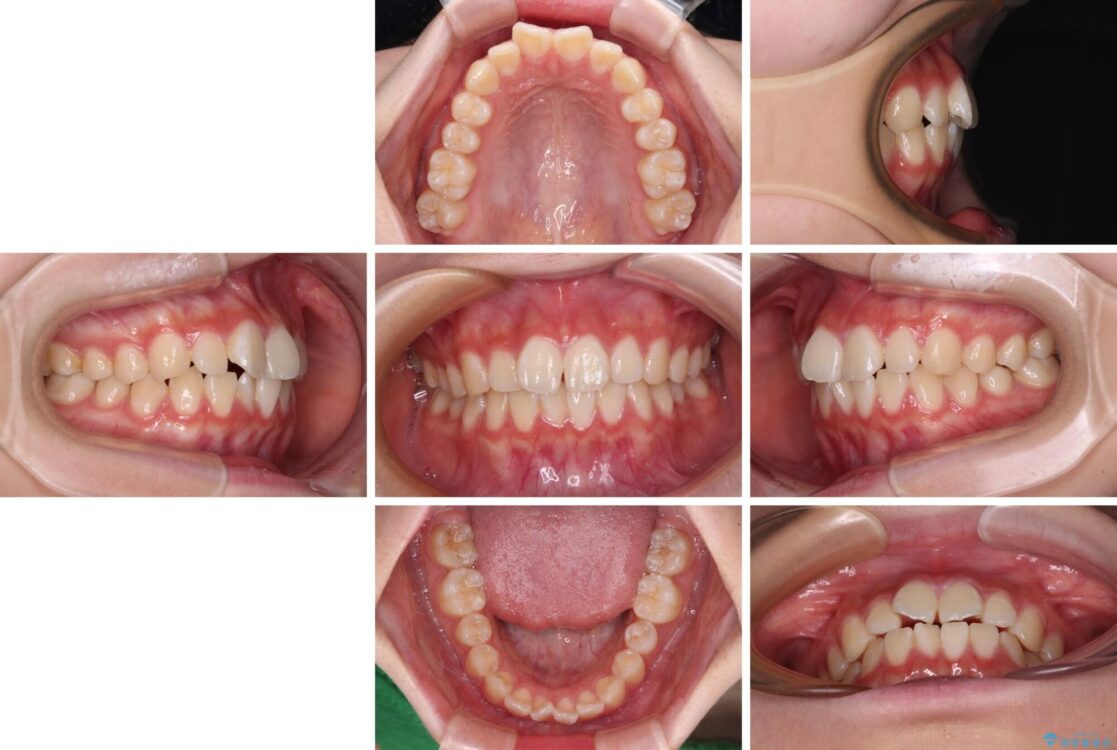

治療前

• インビザラインは使える自信がない ワイヤー装置にて矯正治療 治療前画像

上下前歯のねじれを気にして来院された患者様です。

ワイヤー矯正でもマウスピース矯正でも対応可能でしたが、マウスピース矯正の自己管理が面倒であること、上顎前歯の捻転が著しいことから、ワイヤー矯正での治療を希望されました。